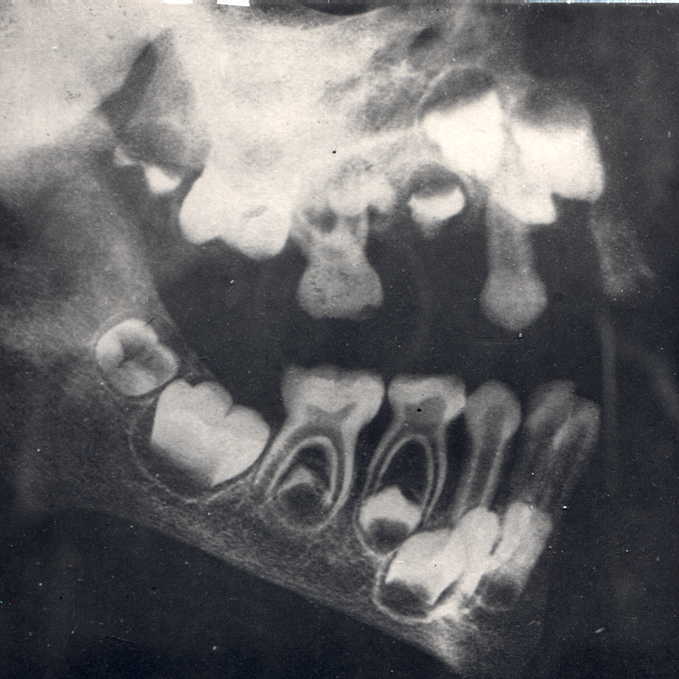

![]() X quang xương và răng hàm trên và dưới trẻ gái 1 tuổi. Theo thứ tự từ Trái sang Phải là mầm răng vĩnh viễn số 6 ( sẽ mọc lúc 6 tuổi ), mầm răng sữa số 5 và răng sữa số 4 đã mọc trong miệng |